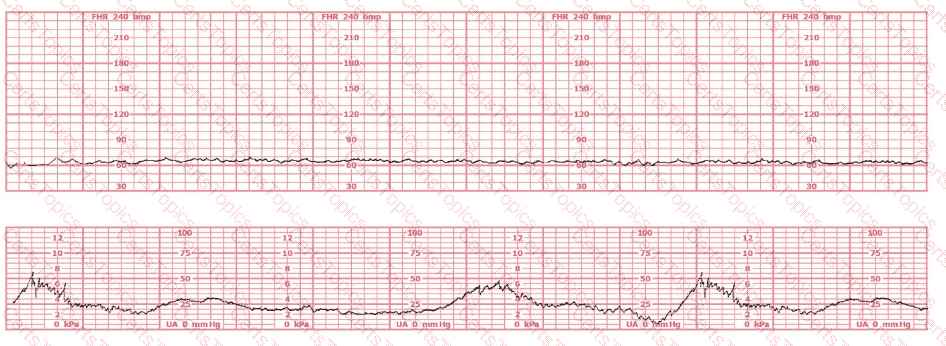

The fetal heart rate tracing shown is obtained upon the woman's admission to labor and delivery. This tracing is most consistent with what maternal condition?

The tracing shown is a:

This tracing demonstrates:

This tracing would be categorized as a